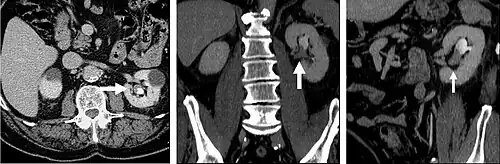

Plain CT urography (without contrast) is used to evaluate stone diseases, calcifications within kidneys, density of renal masses and presence of any bleeding before contrast is given. Then iodinated contrast is given intravenously to evaluate kidney tumours (if any) and urinary tract. CT scan is then taken at 30 to 70 seconds (when the contrast reaches the renal cortex and renal medulla) to evaluate the perfusion and vascularity of the kidneys. CT scan taken at 90 to 180 seconds (when the contrast perfused the whole kidney) to evaluate the characteristics of kidney masses. The contrast starts to drain into the collecting system of the kidneys at 3 minutes after injection and the whole collecting system is well distended with contrast at 8 to 10 minutes. Taking a CT scan at this time is useful to evaluate any strictures or masses from within the ureters or from outside but compressing on the ureters.[2] Contrast CT urography is also useful to monitor whether a tumour is responding to treatment.[3][4]

CT urography (CTU) is commonly used in the evaluation of hematuria, and specifically tailored to image the renal collecting system, ureters and bladder in addition to the renal parenchyma.

The CT scan will image the urinary tract, including the kidney, ureters, bladder, and urethra.[3] It does this by taking many cross-sectional images that can be computationally arranged so as to provide 3D information.[3] The scan itself usually involves a CT scan without contrast (a non-contrast phase), a CT scan while the contrast is within the kidneys (a parenchymal phase), and a CT scan taken while the contrast travels through the renal tract (an excretory phase).[4]